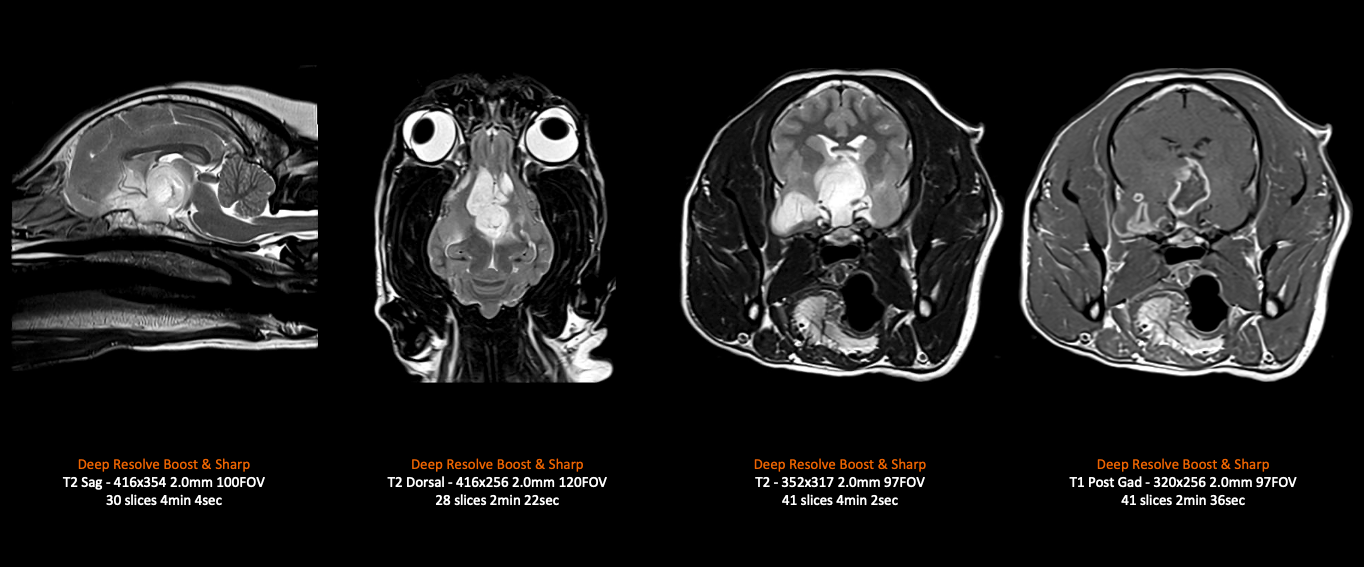

The intuitive AI-based software can be tailored to the specific needs of Vet imaging, with simplified and guided workflows. Incorporating our latest deep learning technology, Deep Resolve, examination times are shortened yet with higher image resolution. This means anesthetic times can be reduced, and less stress on our furry friends. The system includes lightweight and flexible coils perfectly suited for high quality animal imaging and providing the best care and comfort. The MAGNETOM Sempra is distinguished by its low operating costs with zero-helium boil-off and integrated Eco technologies that saves power to reduce overhead costs.